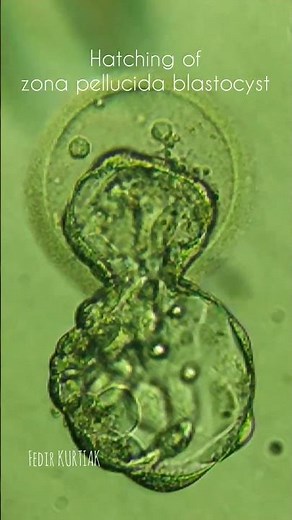

Hatching Blastocyst 的热门建议 |

Blastocyst - Embryo

Development - Blastocyst